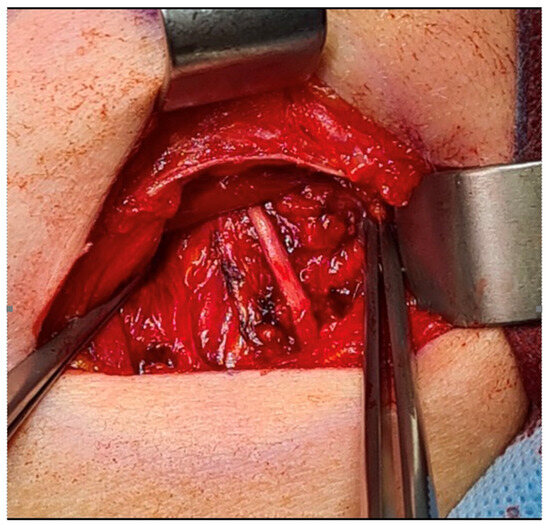

It is with great pleasure that I invite you to submit articles for the “Interesting images” Special Collection. Since we introduced Interesting Images as an article type in Diagnostics, it has served as a valuable resource for the imaging community. Many have relayed that they use these image-based case reports when encountering challenging cases or images of diseases rarely seen. Further, pitfalls are covered by this type of article and may be helpful both for experienced and less experienced image readers in making a correct evaluation.

The interesting Images together serve as a live imaging atlas covering PET, CT, MRI, and other imaging modalities. Therefore, the more cases we publish, the more likely it is that image interpreters with a difficult case can be supported by previously published cases. Although focus until now has largely been on clinical cases, it should be noted that nonclinical cases are also welcome, e.g., from preclinical in vivo imaging, including optical imaging as well as histology images from pathology.